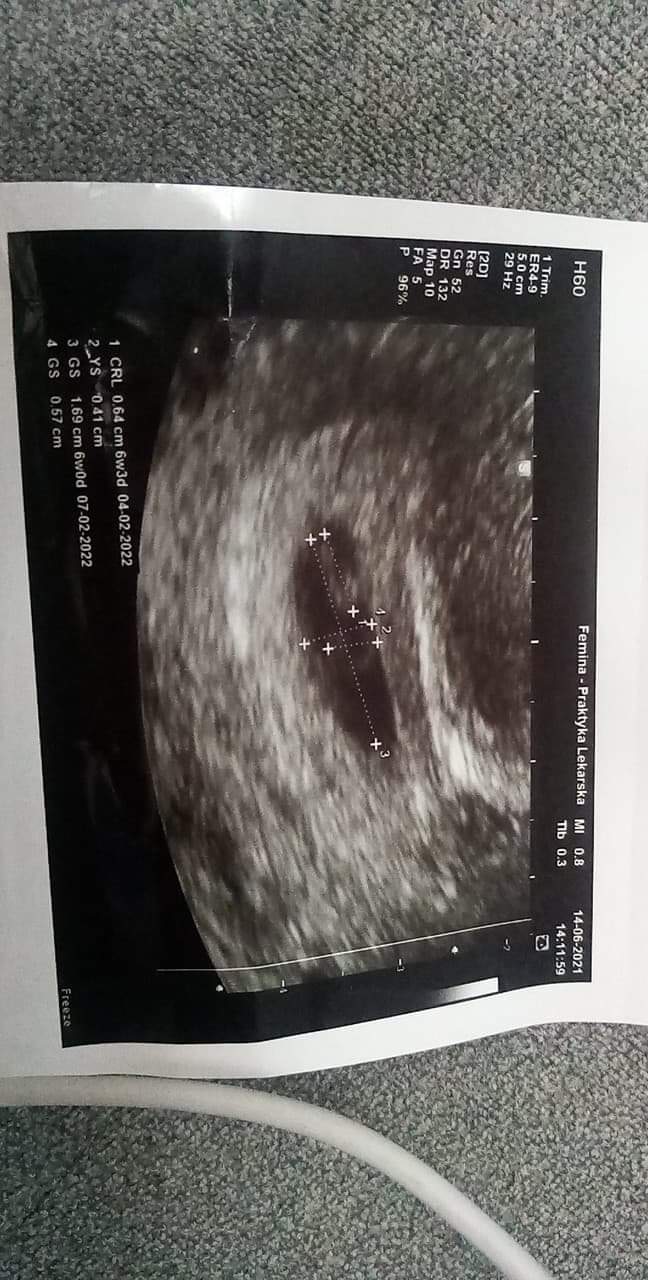

To mamy ten sam termin z USGDawno mnie nie bylo ale dość słabo sie czułam. Wymioty, mdłości, senność i brak mocyale dzis mialam wizytę wkoncu i piękne moje maleństwo jest. Dokładnie 6tc+5dni. Z OM termin porodu na 2 luty 2022 a z USG 4 luty

serduszko pięknie biło więc jestem szczęśliwa

Zobacz załącznik 1282801